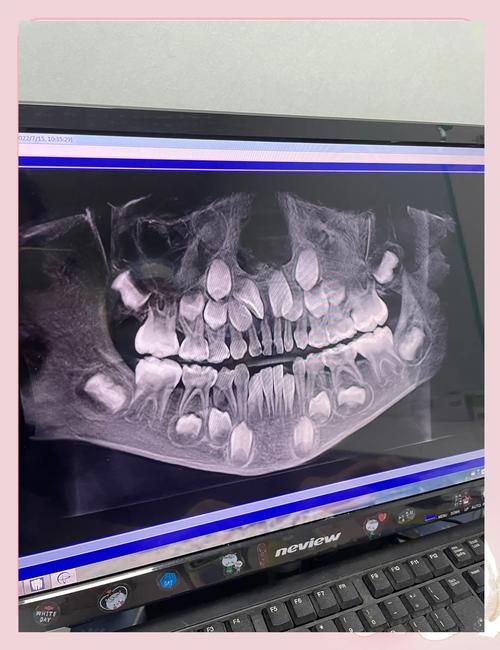

(图片来源网络,侵删)